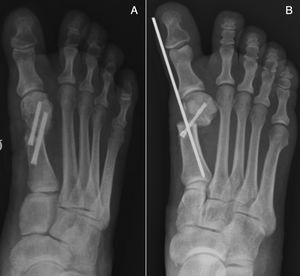

Walking in a post-operative shoe with immediate weightbearing is also allowed. Weekly dressings are prescribed and the Kirschner wire is removed in the clinic in the third post-operative week (Figs. 3 and 4).